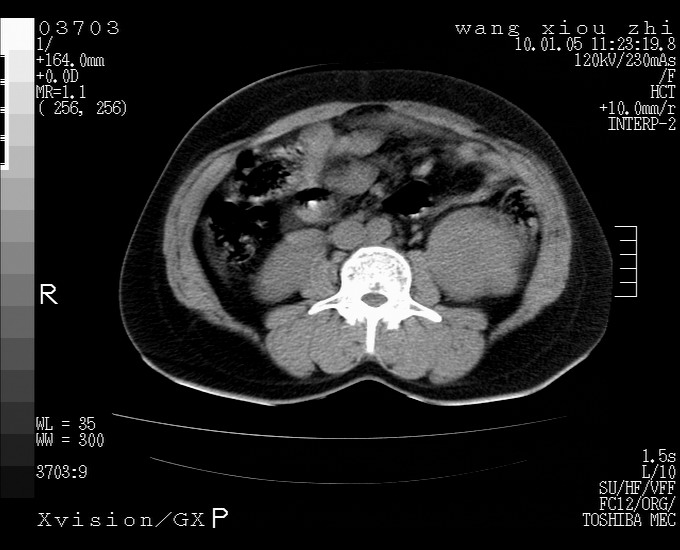

标题: CT23996:f,40.B超提示肿物。 [打印本页]

标题: CT23996:f,40.B超提示肿物。

左肾体积增大!下极见一密度略高团状软组织影!肾周结构组织未见明显异常!考虑左肾占位!建议增强!病史?

左肾占位,肾门及腹膜后淋巴结肿大,考虑透明细胞癌可能性大,建议增强

左肾体积增大,内见肿块影,考虑占位,建议增强。

左肾占位考虑肾癌

左肾占位性病变,不排除肾癌可能;建议行进一步检查。